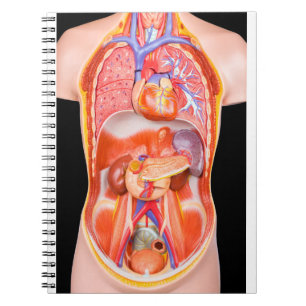

Kroppsmodell hos människa med organ vykort

Pris21,00 kr

Kroppsmodell hos människa med organ anteckningsblock

Pris150,00 kr

Kroppsmodell hos människa med organ vykort

Pris21,00 kr